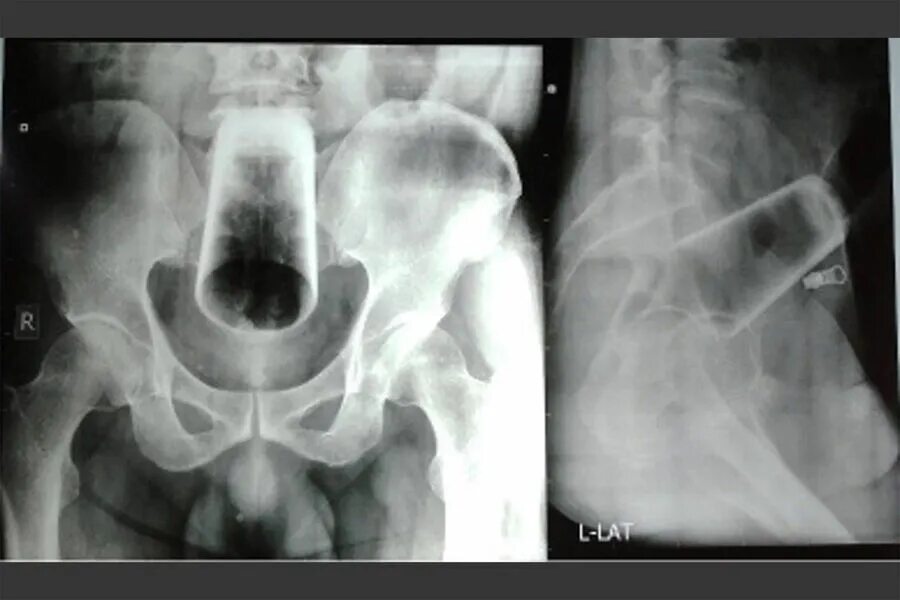

Предметы которые достают из